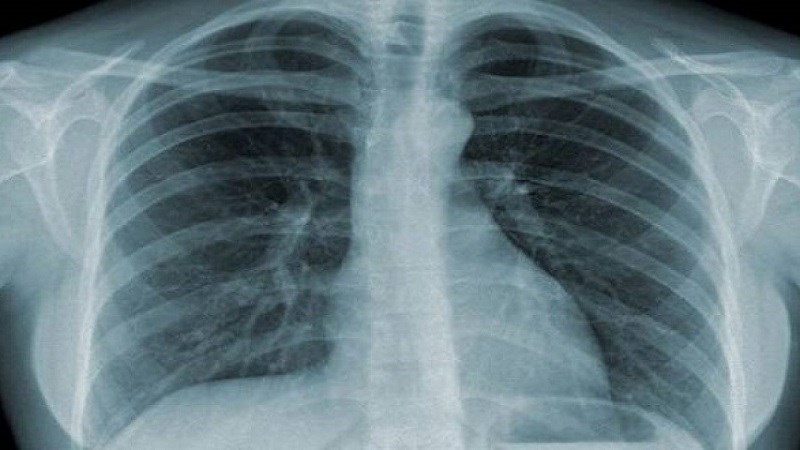

- X-quang phổi thường quy: Có hình ảnh thâm nhiễm, nốt, hang là gợi ý của bệnh lao. Có thể thấy hình ảnh co kéo ở 1/2 trên của phế trường, có thể 1 hoặc 2 bên.

X-quang phổi có giá trị sàng lọc cao với độ nhạy trên 90% với các trường hợp lao phổi AFB(+). Tuy nhiên, độ đặc hiệu không cao nên không được khẳng định chẩn đoán lao phổi chỉ dựa trên xét nghiệm này.

Ngoài ra, X-quang phổi còn có tác dụng đánh giá đáp ứng với điều trị thử bằng kháng sinh thông thường trước khi chẩn đoán lao phổi không có bằng chứng vi khuẩn và để đánh giá kết quả điều trị lao sau 2 tháng và kết thúc điều trị.

Chụp X-quang phổi có giá trị sàng lọc cao lên đến 90%